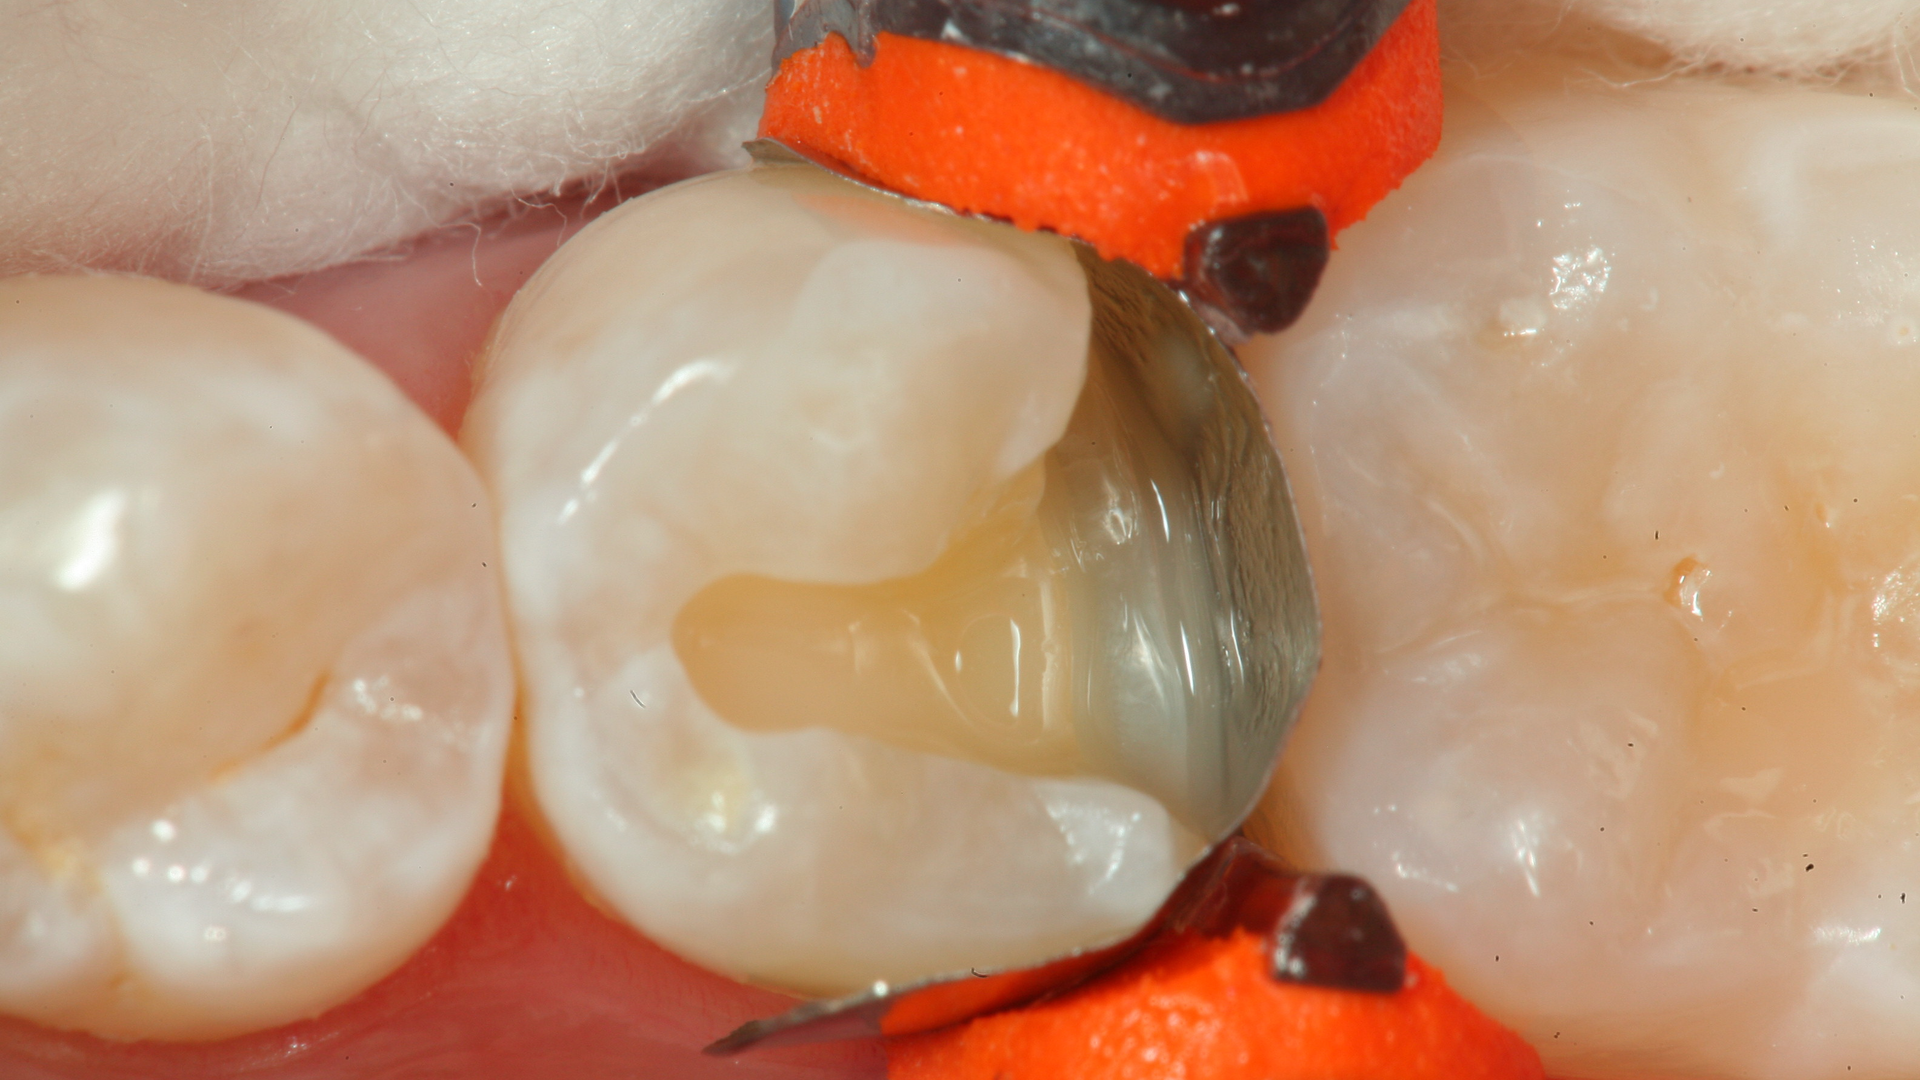

A 68-year-old patient presented with the upper right first premolar with occlusal amalgam and two distal marginal ridge fractures and discoloration under the mesial marginal ridge (figure 1). He previously had an extraction due to a fracture on his lower arch and wanted to treat the upper first premolar proactively. The existing occlusal amalgam was removed under rubber dam isolation. Caries were visualized clinically, and cracks were visualized with transillumination under both marginal ridges (figure 2). The premolar was prepared using a nonretentive cavity preparation design to allow the resin to flow in, out, and around the tooth (figure 3). Particle abrasion with 27 microns at 40 psi (PrepStart, Danville Products) was completed for microretention and biofilm removal before matrices, phosphoric acid etch (figure 4), and adhesive were placed.

The packable ceramic-modified nanocomposite was warmed at 155o F in a composite warmer (figure 5) and applied with an injection-molded technique. In this technique, an increment of flowable composite (Admira Fusion Flow, Voco) was placed first at the deepest level of the restoration and cured. A subsequent layer of flowable was placed at the deepest portion and up the buccal and lingual line angles, and not light cured. The tip of the warmed, packable composite was then placed into the uncured flowable and injected into the flowable under pressure, displacing the uncured flowable and allowing the bulk-fill packable Admira Fusion x-tra (Voco) to restore the majority of the preparation.

Polymerization was completed in a three-point light-cure technique, curing from the occlusal, buccal, and lingual surfaces with and without separators and wedges present. Final contouring with discs and polishing brought the spectral highlights of the composite to a high luster (figures 6 and 7). Occlusal evaluation was completed along with a postoperative radiograph (figure 8). The patient reported no postoperative sensitivity.